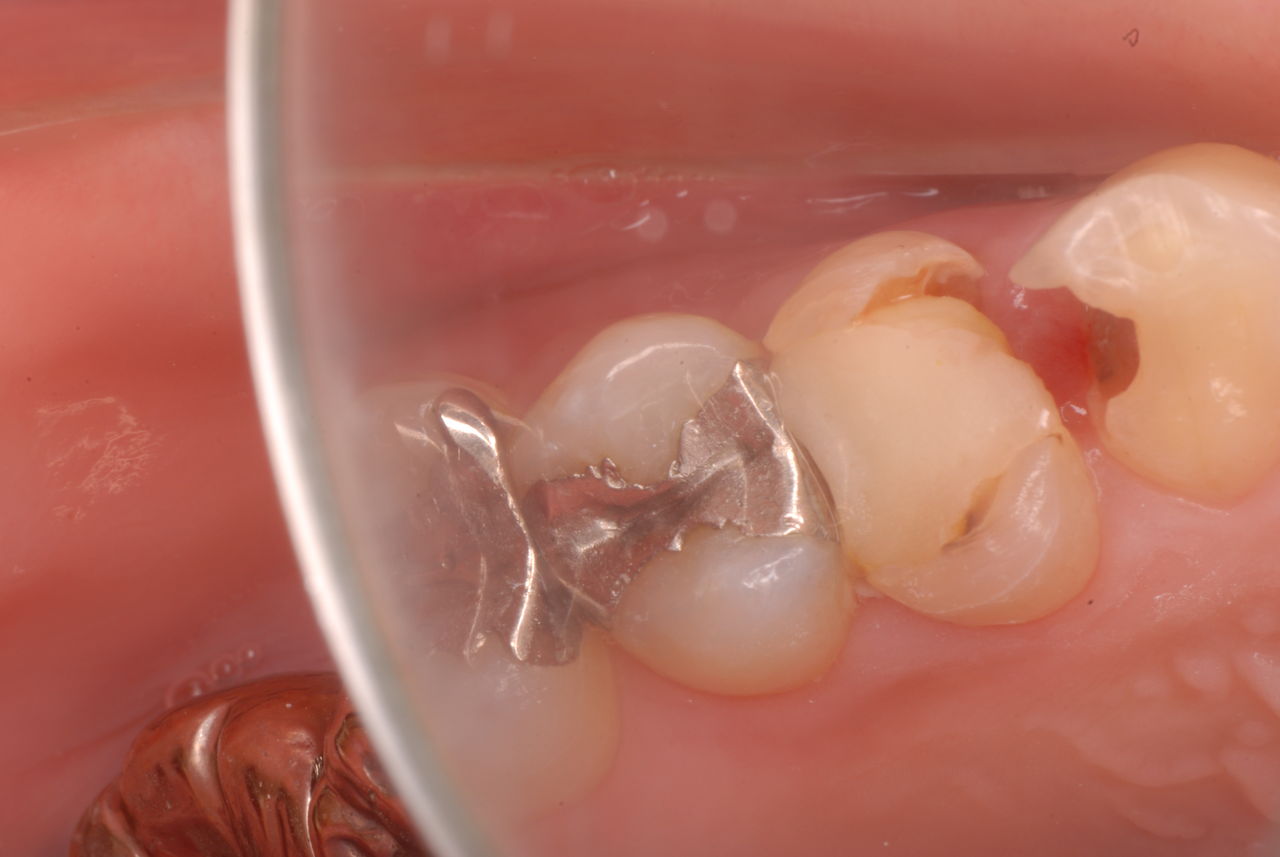

入れ歯の話から入りました。色々不満で注文があるようです。でも話が一段落して口腔内を調べると殆どの歯が重症で抜けそうな歯だらけなのです。

色々不満な入れ歯です。

発音や見える金属が気になるようです。

ご自分でやられても歯茎から血が出ないと話をされていましたが、私がブラシを当てると悲惨な状態であることがわかりました。

何故歯が悪くなるのか、歯周病で抜けるのか分からなければ何を入れても歯は悪くなり抜けていくのです。